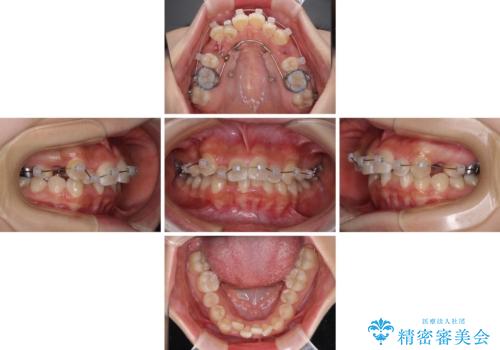

奥歯の咬み合わせを見ると、上顎臼歯が下顎に対して前方にあり、叢生改善により口元が突出する顔貌ではなかったため、上顎左右第一小臼歯2本を抜歯し、ワイヤー装置にて矯正治療を行うこととしました。

前歯部のデコボコがなくなったため、歯磨きしやすくなり、非常に清潔な状態になりました。